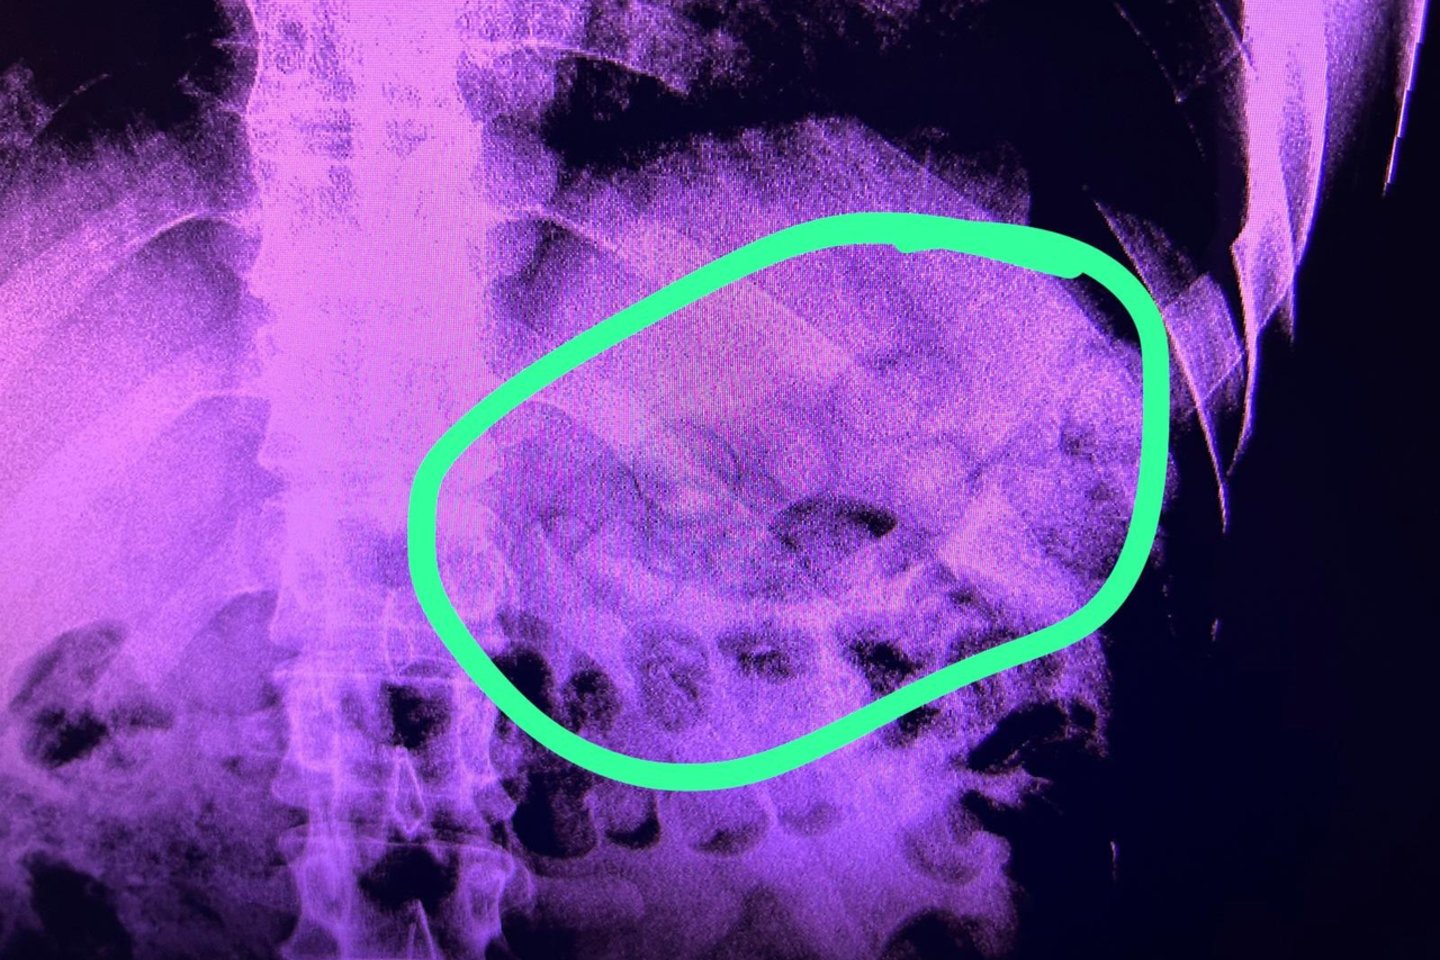

Šių metų kovo 3 d. Pravieniškių 1-jame kalėjime, pareigūnams tikrinant nuteistuosius, grįžtančius iš išvykos į pusiau atviro tipo bausmės atlikimo vietą, įtarimų sukėlė vieno nuteistojo elgesys. Įvertinę apie asmenį turimą informaciją, pareigūnai jį pristatė į Lietuvos sveikatos mokslų universiteto Kauno klinikas. Medikams jį apžiūrėjus ir atlikus tyrimus, nustatyta, kad nuteistojo skrandis yra pilnas apvalios formos paketėlių, kuriuose buvo galimai narkotinės medžiagos.

Skrandyje aptikus svetimkūnius, bausmę atliekantis asmuo pats patvirtino, kad į įkalinimo įstaigą bandė įnešti keletą paketų su galimai narkotinėmis ar psichotropinėmis medžiagomis, kuriuos prieš grįždamas į įkalinimo įstaigą prarijo.

Turimais duomenimis, nuteistasis iš viso galimai bandė pergabenti apie 11 paketėlių.